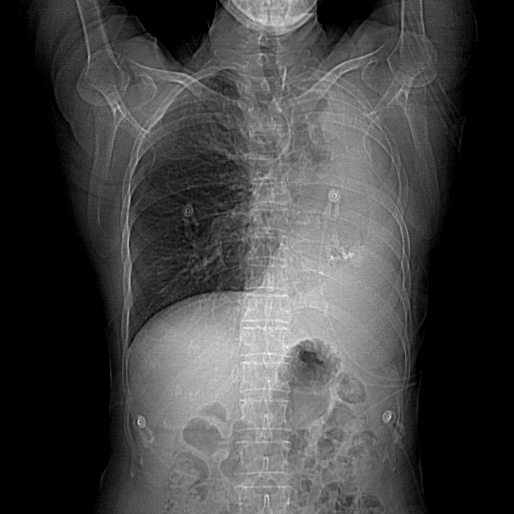

患者17年前因肺结核行左肺叶切除,术前CT结果显示,心脏转位完全偏至左侧胸腔,主动脉弓被挤压成角非常锐利。患者为二叶式主动脉瓣 Type 1型,R-L融合大块钙化脊,且钙化赘生物垂坠至瓣环平面,导致“lazy leaflet”瓣叶结构,主动脉根部极重度钙化,风险度极高,球囊扩张时合并极高的瓣环破裂风险,也可能无法推动钙化使瓣膜形态变形导致严重瓣周漏等并发症。瓣环面积为588.8mm2,平均内径为27.4mm。考虑到患者已行开胸手术,身体虚弱,外科手术风险较高,且介入治疗可更快恢复,减少住院时间,经心脏团队讨论,并与家属协商后,计划行经导管主动脉瓣置换术。

图2. 主动脉根部极重度钙化与lazy leaflet结构